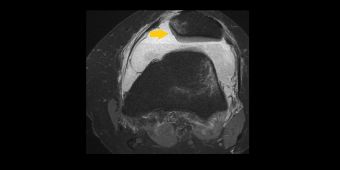

- Patelladysplasie und -luxation: Bei dieser Fehlbildung besteht keine ausreichende knöcherne Führung und Halt der Kniescheibe (Patella), die aus ihrem Gleitlager herausspringen (luxieren, Bild ) kann. Die Behandlung erfolgt je nach Ausmaß der Fehlstellung konservativ oder operativ